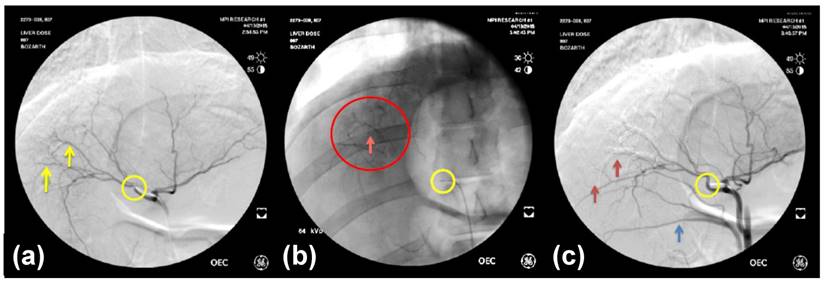

Imaging Appearance of Embolized Livers

All radiopaque beads, regardless of drug dose, administered during both the phase one and two studies were visible on fluoroscopy and DSA post embolization and contrast wash-out (Figure 2), and on CT (given their high attenuation) both with and without contrast. There was no detectable difference in visibility between the drug loaded bead groups at the three different drug concentrations in the phase one study (Figure 3). In all cases the beads could be seen in hepatic arteries within the embolized lobes, with relatively distal penetration consistent with the size of the beads and lack of proximal aggregation.

(a) DSA pre-embolization showing arteries to be embolized (yellow arrows); (b) Fluoroscopic image post-embolization and contrast wash-out showing VERB100 in arteries (red circle); (c) DSA post-embolization showing shadowing imaging artefact from the radiopaque beads in the arteries (red arrows). Catheter tip position is shown in the yellow circle and the blue arrow points to reflux of contrast in a more proximal arterial branch related to distal embolization.

Despite the increase in density due to the introduction of iodine species to provide radiopacity [35], VERBs were easily handled by suspension of the 2 mL of hydrated beads in 18 mL of soluble contrast agent, followed by slow administration at a rate of around 1 mL of suspension per minute. The beads could be clearly seen on fluoroscopy as they accumulated in the hepatic vessels and the soluble contrast washed away (Figure 2) [43]. Despite this, some off-target embolization was expected as attempts were made to deliver the full dose of 1 mL of beads, which was achieved in most cases. The radiopacity of the VERB embolic device was shown to be useful not only during delivery for targeting the beads, but at follow-up by CT for identifying bead location and associated imaging findings such as decreased hepatic parenchymal enhancement in the treated locations, embolization-related lobe size reduction and bile duct dilation. Biliary dilatation is likely indicative of hepatic artery ischemia caused by the embolization, because the biliary ducts are supplied by hepatic arteries rather than portal vein blood supply. There was no obvious difference in the radiopacity between VERB with different drug doses used in the phase one study, despite the drug potentially contributing slightly to the overall radiopacity due to the presence of radiodense bromine atoms on the drug structure [34]. The radiopacity of the beads did not change over the 90 day period confirming the stability of the device as demonstrated previously with this radiopaque platform [37].